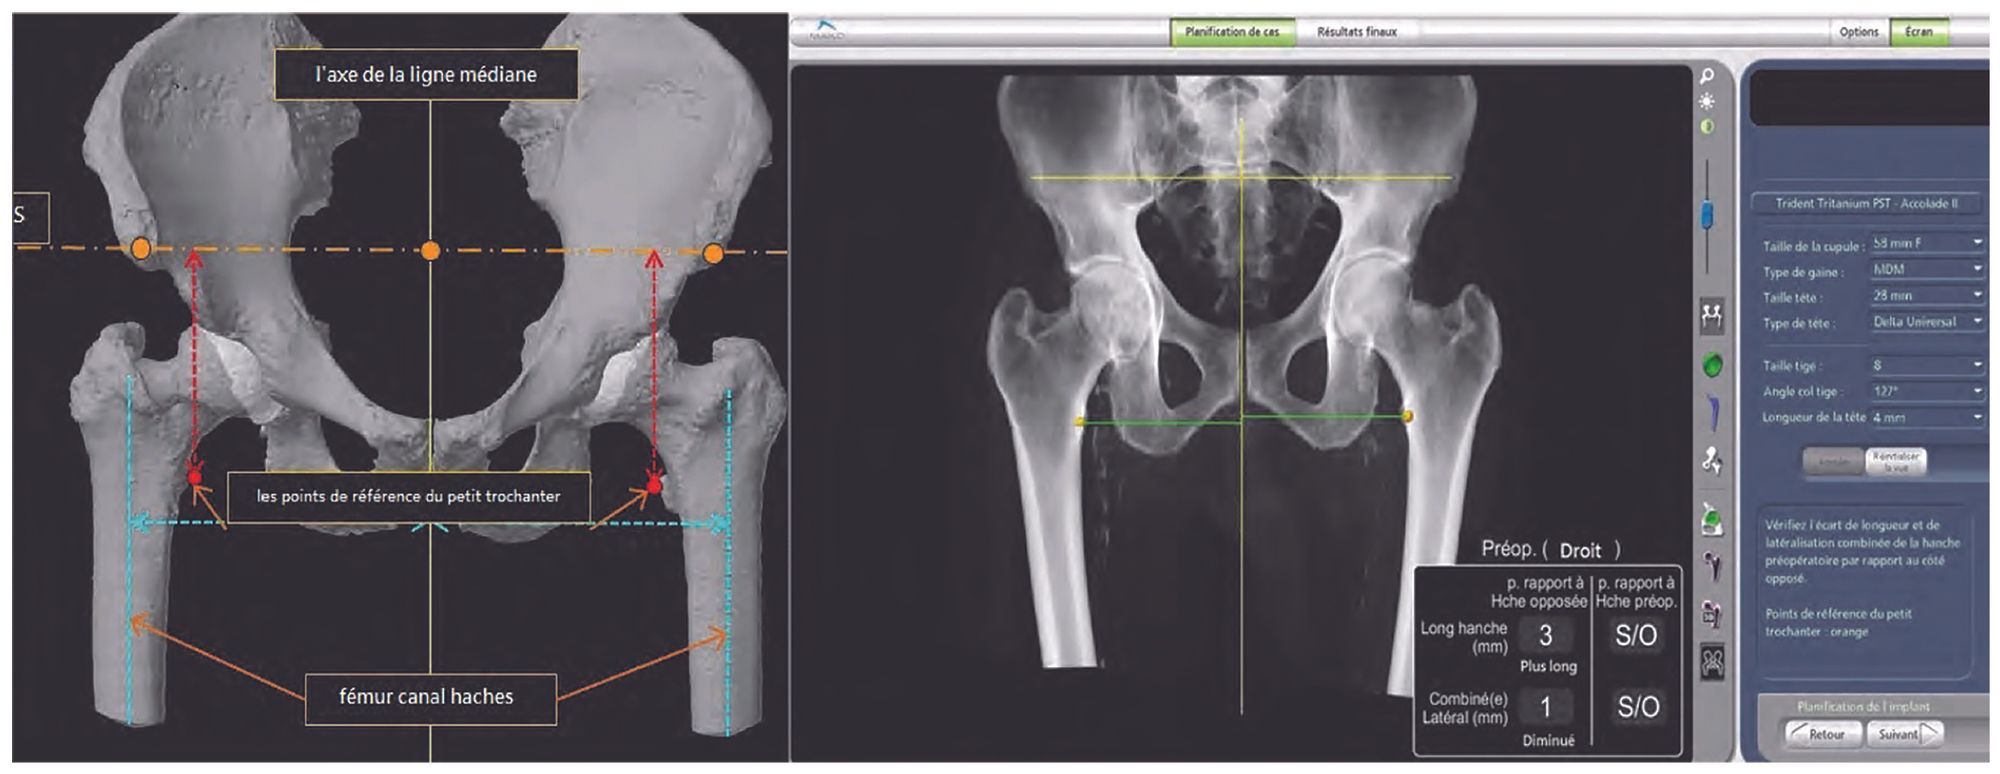

The robotic arm comes with software with the ability to plan implant placement using patient-specific anatomic markers and native acetabular geometry, centre of rotation, femoral version, offset and comparative length of the operated hip.

For a total hip arthroplasty (THA), the patient data are collected in advance using a preoperative CT scan with the ability to calibrate the field (knees can be included in the field in order to assess femoral version). Once the CT scan is complete, the specialist Segmentation Team creates a patient-specific virtual 3D model of the pelvis and femur. Using the surgeon’s preferences, the Segmentation Team will also create an initial pre-plan and select the CT landmarks.

One of the key stages prior to the procedure the surgeon’s approval of the plan proposed by the MPS (Mako Product Specialist) or engineer. The surgeon has complete flexibility, during the preoperative planning, to adjust various components of the plan based on the implant used, including:

The surgeon is responsible for ensuring the appropriate location, type and size of the incision. This choice will influence the position of the landmarks. The pelvic array is placed on the iliac crest, on the same side as the approach if posterior, or on the opposite side as the approach if anterior. The acetabular and femoral landmark placement will also depend on this choice (Fig. 5).

The landmarks are used to reconcile the navigation data with the anatomic data collected preoperatively and adjust the robotic arm for placement of the reamer and final implant. They are also points of reference for guiding the femoral stem. Once the femoral array is in place, the surgeon collects the preoperative length and offset of the native hip. After resecting the femoral neck, exposing the acetabulum and placing the acetabular landmark, the software correlates the checkpoint acquisition data (mapping) with the plan. If following the enhanced workflow, the femoral checkpoint acquisition will precede the acetabular checkpoint acquisition (Fig. 6).